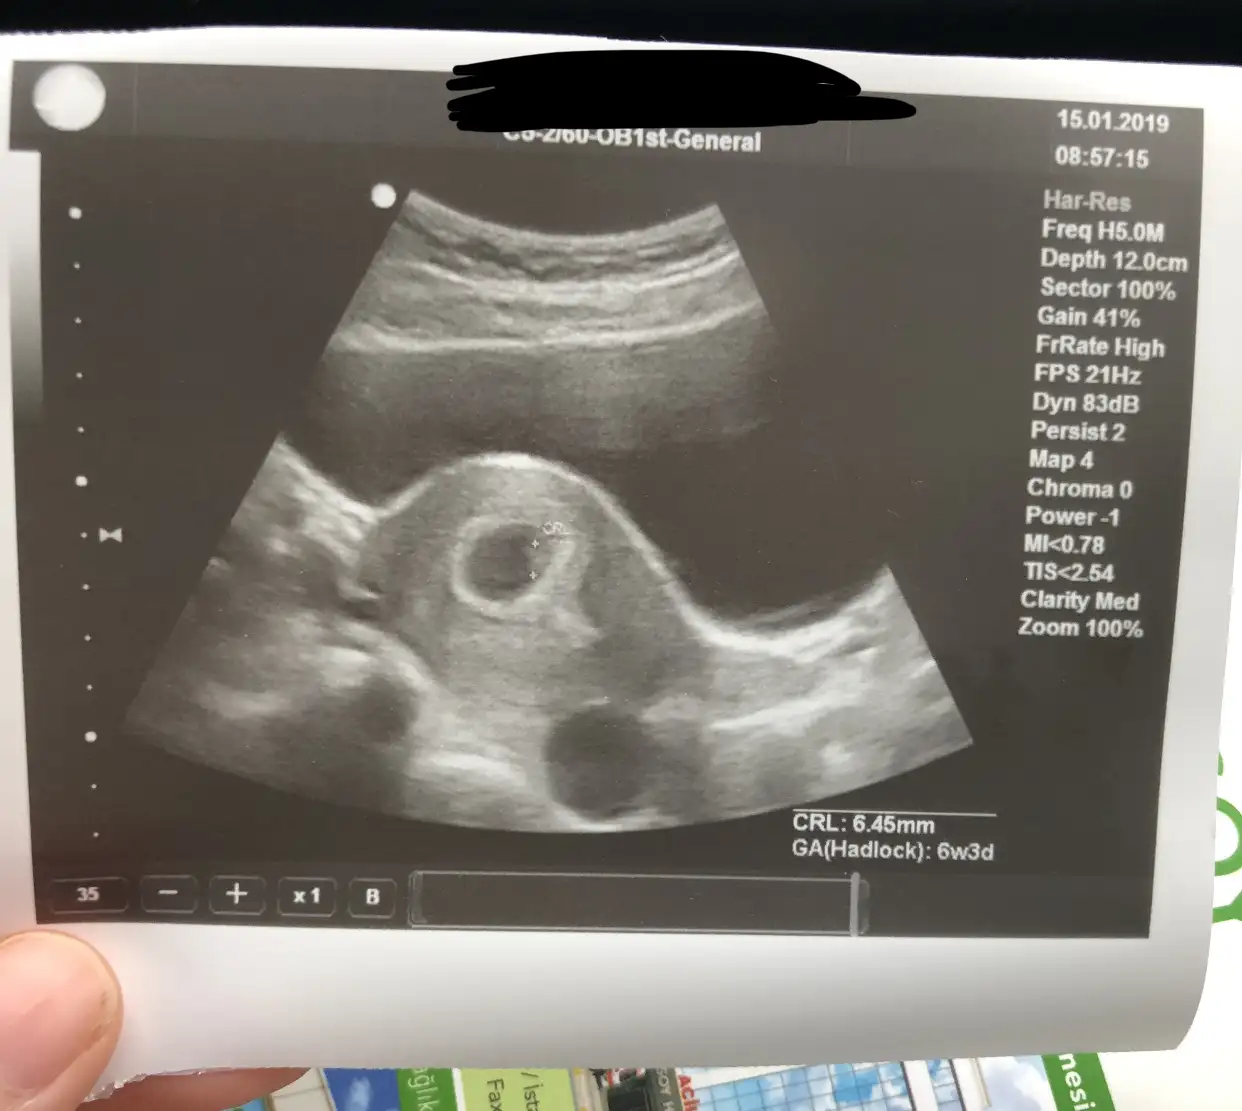

Aaaaa canim bundan hic haberim yoktu. Bak benim 6 haftalik ultrason goruntum. Bakalim tahminin ne olacak? ☺goruntude anlasiliyor mu bilemedim ama sag ust tarafts doktor isaretlemisti. Bu goruntu karindan.

Kızlar karından olup sağda olursa kız oluyor ,solda olursa erkek oluyor. Vajinal da farklı oluyor, tek bebeğe göre yapmıyorum birde kesenin etrafın bakıp yapıyorum çoğu tuttu:)